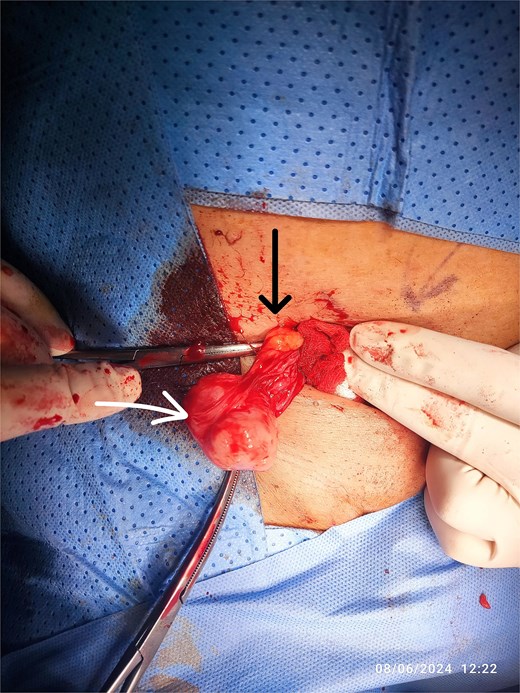

A right inguinal incision was made, and the mass was identified within the spermatic cord. The encapsulated mass was excised completely with a safe margin (Fig. 2). Histopathological examination revealed an intermediate-grade leiomyosarcoma with a positive resection margin, with mitosis (20/1000 cells); immunohistochemistry shows Ki67—2%, caldesmon—positive. In light of the positive margin and the malignant nature of the tumor, the patient underwent a second surgery 2 weeks later.

Intraoperative view of the RT inguinal mass (white arrow), cord structures (black arrow).